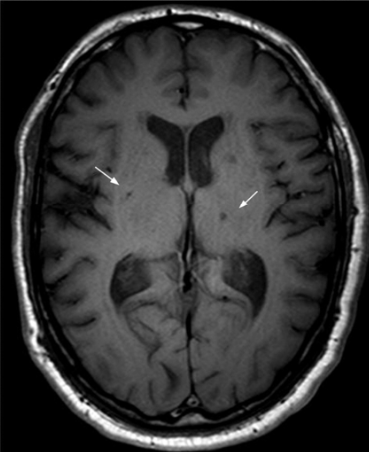

this infarct is a small lesion less than 5mm in diameter. found in short penetrating arterioles of basal ganglia, pons, cerebellum, internal capsule/ assoc with uncontrolled HTN, DM.

lacunar infarct

pt has pure contralateral motor deficits, pure c/l sensory deficits, ipsilateral ataxia, dysarthria with hand clumsiness.

prognosis of lacunar infarct

deficits stabilize withing 24-36 hrs and generally have good prognosis at small size